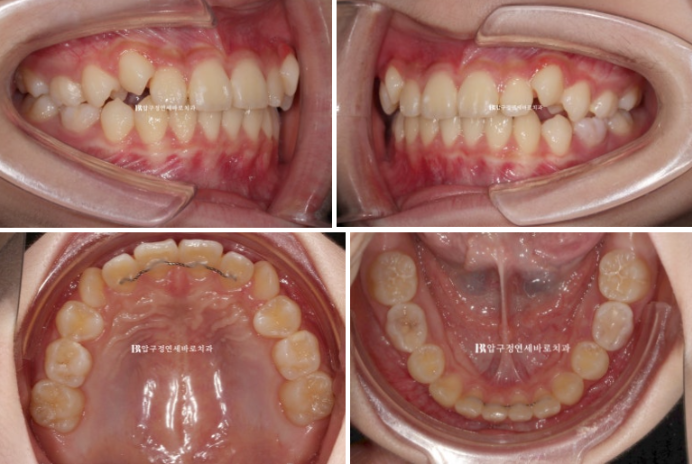

24.09

중심선은 정확히 맞고

어금니 교합은 1급 교합관계를 보입니다.

배열도 좋습니다.

그 사이 마지막으로 맹출하는 두번째 큰어금니까지 잘 나오고 있습니다.

소아교정장치로 시작했지만 성인때 교정을 다시 할 필요가 없을 정도로 모든 게 좋습니다.